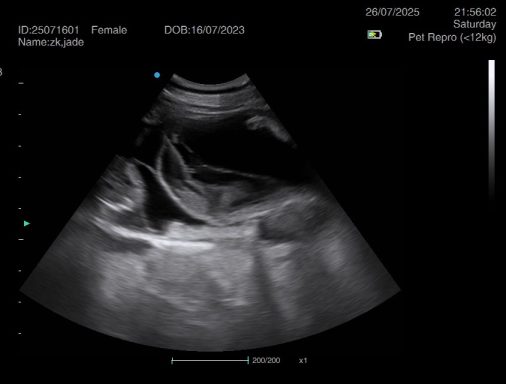

Ultrasound pregnancy scanning is a safe, non-invasive way to confirm pregnancy in dogs and cats, offering breeders and pet owners peace of mind and vital information to support responsible care. It allows us to detect gestational sacs, assess foetal development, and estimate litter size—all while ensuring the wellbeing of the animal.

For the most accurate and reliable scan, we advise booking between Day 25 and Day 32, when pregnancy is more easily confirmed and foetal structures are clearer. If an early scan is performed and no pregnancy is detected, we offer a FREE complimentary re-scan after 7 days at the clinic to ensure clarity and support informed decision-making.